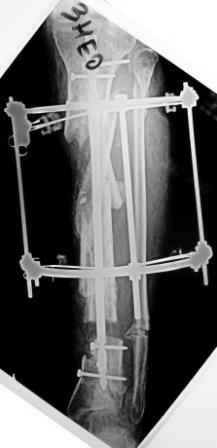

Коллеги!Позвольте продолжить обсуждение темы «ложный сустав левой голени.» Больной К 45 лет, начало см. http://www.weborto.net/forum/1228422607/ И рассказать о результатах проделанной работы. Остановились на следующей тактике 1) Наложить Аппарат Илизарова. В аппарате восстановить оси трех смещенных относительно друг-друга фрагментов большеберцовой кости. Устранить вальгусную деформацию дистального отдела большеберцовой кости. Что и было выполнено. - Была выполнена репозиция в аппарате (рис1) 2) После репозиции более очевидна стала проблема дефекта кости в верхней трети голени, два фрагмента свободно лежат. Остановились на варианте перехода на интрамедуллярный синтез стержнем с покрытием костный цемент+ванкомимцин и замещении дефекта с помощью транспорта фрагмента (рис 2) 3) Третьим этапом наложили модуль на промежуточный фрагмент.(рис 3) И начали его транспорт на стержне в проксимальном направлении. (рис 3 а) Надеемся что «вырастет» регенерат в дистальном отделе, а в проксимальном отделе фрагмент «упрется» и прирастет. Хочу сказать слова благодарности за обсуждение на форуме этого случая. Особые слова благодарности Иванову Павлу Анатольевичу!!! Он помогал Словом, а самое главное делом. Приезжал, оперировал! За что ему нижайший поклон! С ув Коробушкин Г

Да, это единственное, что "царапает глаз" при разглядывании этой интересной серии снимков.

Мы сейчас обычно вводим отклоняющую спицу еще пока голень лежит на столе горизонтально, до сгибания в колене для формирования канала и т.п.

Для восстановления оси "по-правильному" надо извлечь гвоздь, ввести отклоняющий винт или спицу, и ввести гвоздь повторно. А пытаться

исправить ось с гвоздем внутри мэтрами, например, проф. Шнеттлером, не рекомендуется. Мы, однако, попробовали - получается. Надо убрать запирающие винты из центрального отломка. В данном случае, при наличии не перелома, а дистракционного диастаза, надо использовать дистрактор. С помощью спиц которого, введенных с гиперкоррекцией, ось и исправить. Раз канал там широкий, получиться должно легко. После чего ввести винт кнаружи от гвоздя, а потом и винты через гвоздь.